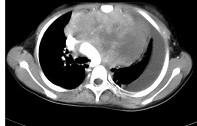

患者胸痛胸闷,CT如图,最可能的诊断为 ( )A.良性胸腺瘤B.恶性畸胎瘤C.侵袭性胸腺瘤D.表皮样囊肿E.淋巴瘤

问题 患者胸痛胸闷,CT如图,最可能的诊断为 ( )

选项 A.良性胸腺瘤 B.恶性畸胎瘤 C.侵袭性胸腺瘤 D.表皮样囊肿 E.淋巴瘤

答案 D